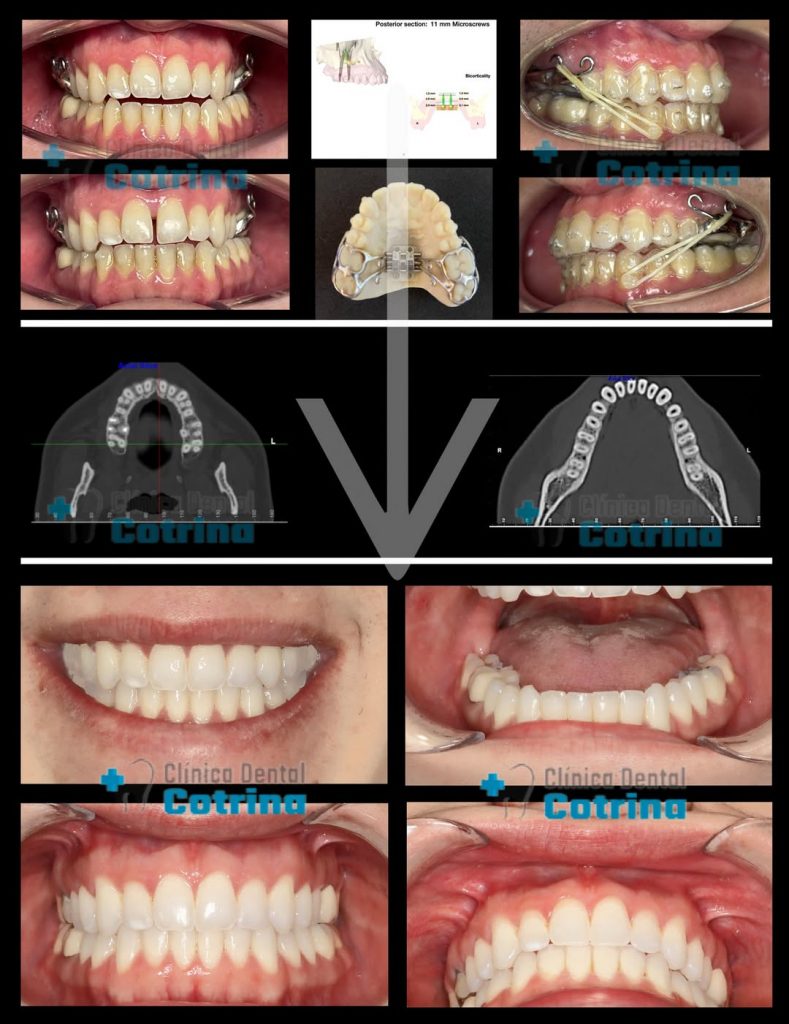

En este caso de paciente adulto que acude a la consulta para realizarse tratamiento de ortodoncia, el motivo de consulta fue que quería mejorar su sonrisa.

Tras el estudio profundo e individualizado realizado a nuestro paciente le aconsejamos una disyunción del maxilar superior ya que su hueso maxilar era más estrecho que su mandíbula y además nos comentaba que tenia problemas para dormir en cuanto a la respiración con ronquidos fuertes y desviación del tabique nasal, tras realizarse un estudio de su respiración con poligrafía respiratoria el paciente referia apnea de sueño muy leve y fuertes ronquidos.

Al ver que el hueso maxilar era pequeño de tamaño quisimos recomendarle expansión del hueso superior con un disyuntor anclado al paladar con microtornillos para tener un hueso más ancho, poder mover los dientes superiores mejor en ese hueso y mejorar la respiración ya que es el suelo de las fosas nasales.

Como además tenia la arcada inferior más adelantada tambien quisimos realizarle un tratamiento previo a Motion clase III que son unas “barras metálicas” que se cementan en la zona posterointerior para poder retruir o “llevar hacia atrás” a esa zona mediante elásticos intermaxilares, una vez conseguido ese movimiento fue cuando realizamos la disyunción y aprovechando el anclaje posterosuperior terminamos de retruir o llevar hacia atrás la zona anteroinferior cerrando los espacios generados de la retrusión (movimiento hacia atrás) de la arcada inferior en su zona posterior cierre de los espacios generados delante de las barras metálicas.

Finalmente observamos unos resultados muy buenos no solo a nivel estéticos, óseo y dentario sino también en la respiración y salud del paciente.

Este tratamiento duró solamente un año y medio y el paciente nos expresó su satisfacción a través un video testimonial que publicaremos próximamente.